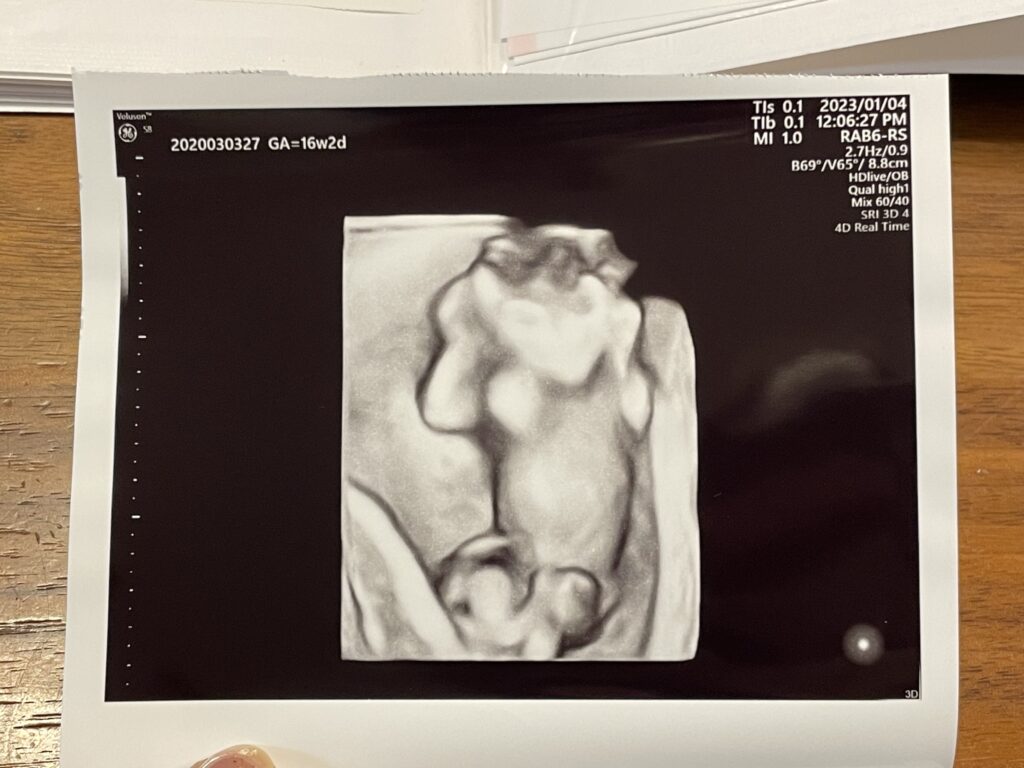

希望したわけではないのですが、お腹からの普通のエコーに加えて途中から4Dに切り替えて見せてくれました。

ちょっと怖かったのですが、お医者さんが「これは頭が透けてしまって見えているだけです」と言ってからは安心してみれました(笑)